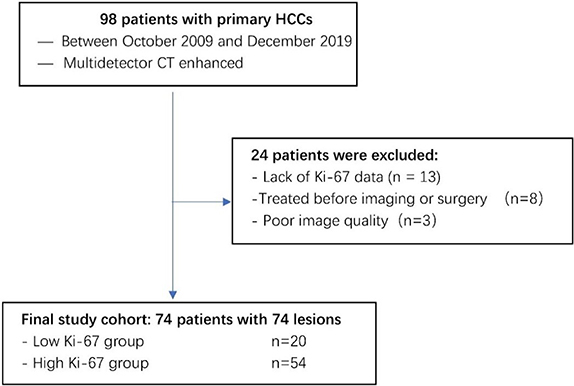

HCC was diagnosed according to the World Health Organization (WHO) criteria of microscopic morphological assessments after surgical resection. A total of 98 patients with primary HCC who had undergone initial CT imaging between October 2009 and December 2019 were selected from the radiology report database. In this study, the inclusion criteria were as follows: (a) confirmation by pathology; (b)complete pathological data, including Ki-67; and (c) complete CT images. The exclusion criteria were as follows: (1) recurrent or metastatic tumors; (2) liver transplantation; (3) incomplete CT images or poor quality; and (4) lack of Ki-67 data. A review of clinical data from medical records found that no patients in this cohort received neoadjuvant therapy;74 patients with HCC were enrolled in this study, as shown in table 1.

3.1. Ki-67 and CT features

The patients were divided into two groups according to their Ki-67 scores: patients with scores of 0 and 1 were classified as the low Ki-67 group (figure 2(A)) and those with scores of 2, 3, and 4 were classified as the high Ki-67 group (figure 2(B)). As indicators such as the mean and variance do not have a normal distribution, all results were expressed as the median and P25 ∼ P75. The low Ki-67 group had a total of 20 lesions, and the high Ki-67 group had 54 lesions. The clinical characteristics of the patients are shown in table 1. An overview of the case selection process is shown in figure 3.

Standard image High-resolution imageFigure 3. Flowchart illustrating subject selection.